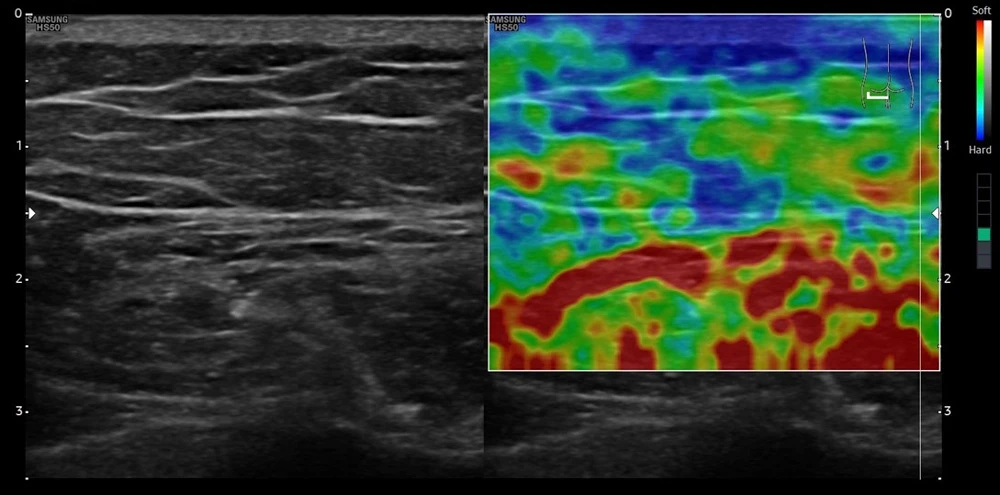

Эластосканы пациента до начала лечения. Левая сторона

При выполнении ультразвукового исследования кожи и подкожно-жировой клетчатки на аппарате экспертного класса линейным датчиком у пациента с целлюлитом в глютеофеморальной зоне до проведения терапии SKINOVA PRO Body при оценке качественной соноэластографии визуализировались участки с более низкой эластичностью (на снимках включения более мягких участков, окрашенных на эластоскане в оранжевые, красные цвета).

После курса лечения у пациента в тех же исследуемых участках при поверхностном сканировании в тех же точках наблюдалась значительно более высокая жесткость ткани (на снимках окрашены в синий и зеленый цвета).

Отмечается увеличение прочности на границе кожи и подкожной клетчатки.